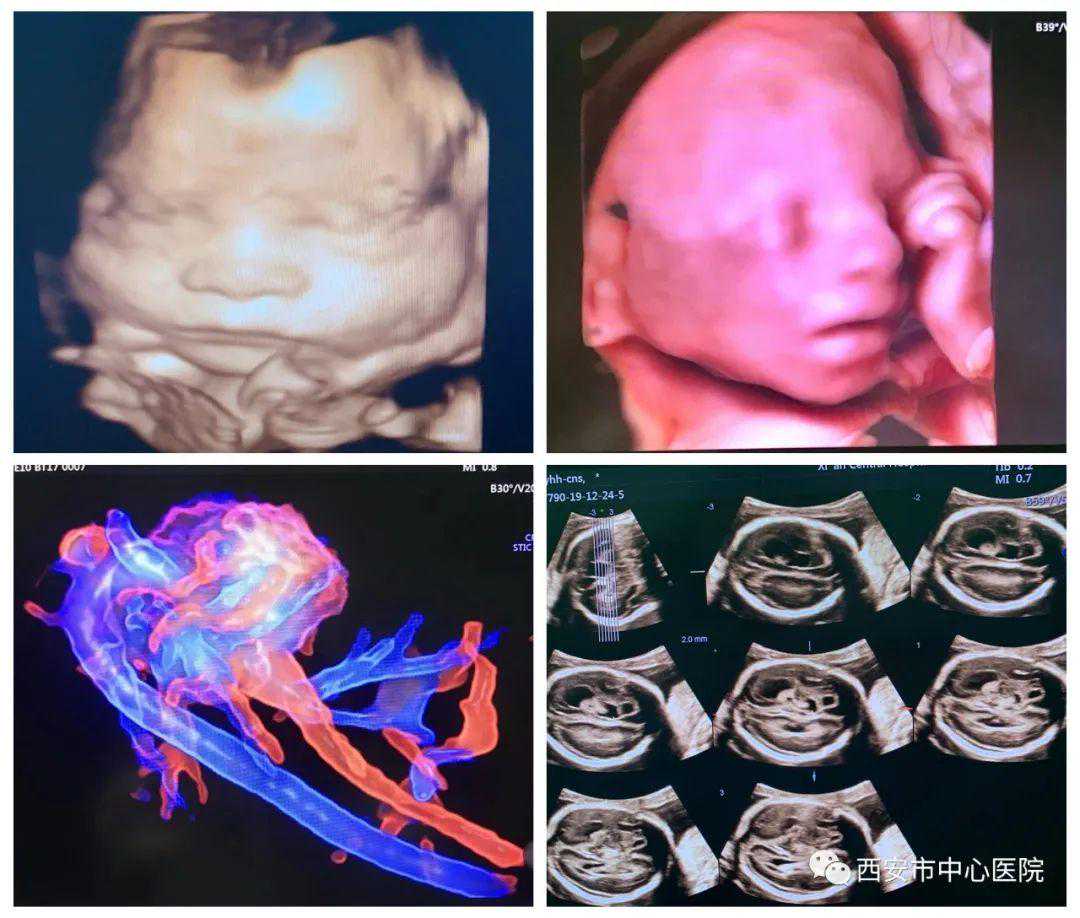

轻度的侧脑室增宽,其往往是一个排除性诊断,该征象可为一些隐匿性的脑发育异常的唯一超声表现,也可以是正常胎儿的颅内声像,同样图像的预后可能存在明显差异,侧脑室宽度持续性小于1.2CM者,通常预后较好,孩子大多正常,大于1.5cm者预后较差(但依然有一部分出生后正常)。发现这类软指标后,超声医生将为胎儿应用容积成像、线断层成像、VCI成像等多种模式进行全面评估,必要时组织科室会诊(所以产检选择仪器先进,技术过硬的团队很重要!)。西安市中心医院超声诊断科是陕西省产前超声筛查中心,配备最先进的VolusonE10、煊光VolusonE8等高端四维彩超,将为大家提供全方位高质量服务,在临床应用上覆盖了生殖医学、产前筛查、早孕期筛查、胎儿心脏、妇科肿瘤等方面,全方位呵护妇女健康。